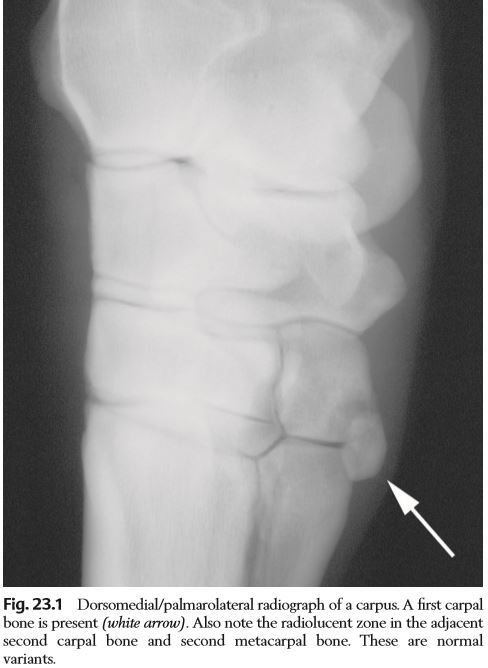

Q

What causes this radiolucency?

A

Incomplete fusion of the epiphysis of radius and styloid process of the ulnar… normal variant